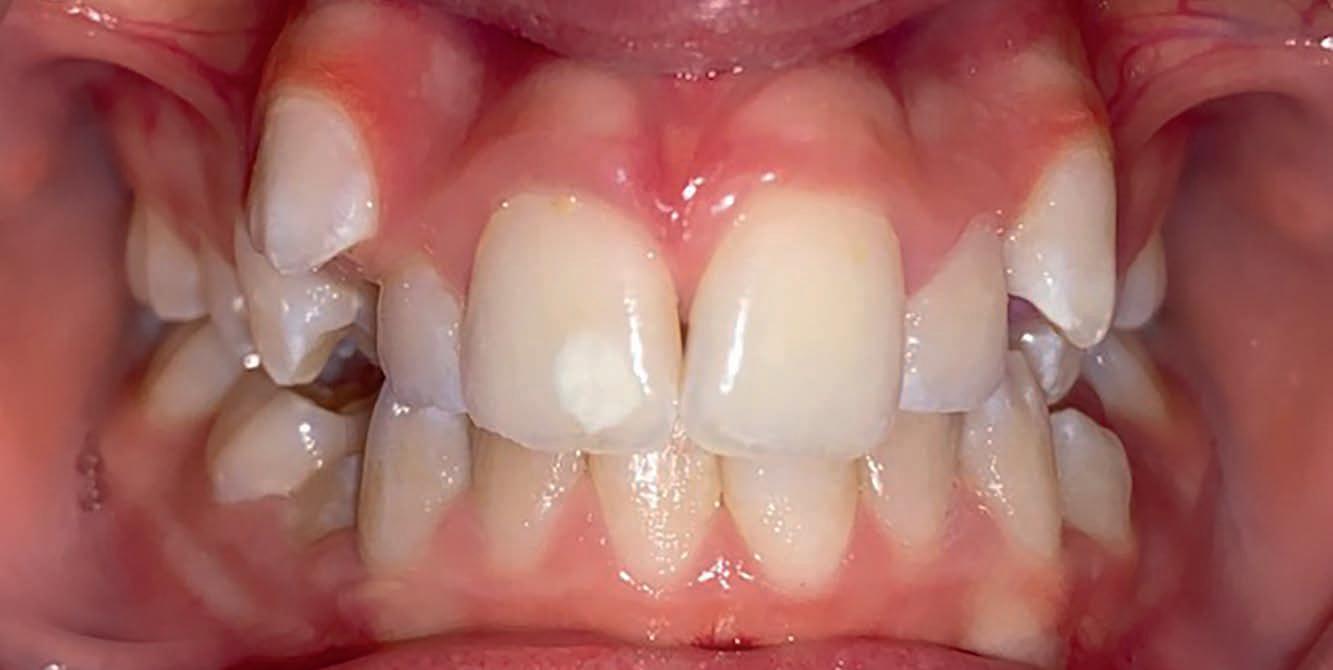

Casus: Blix – Ruimte creëren zonder extracties met D-gainer en Damon Ultima Blix (10 jaar) presenteerde zich met een klasse II-occlusie, smalle boven- en onderkaak en ruimtegebrek voor de doorbraak van de hoektanden en premolaren. Hoewel haar gezicht in balans was, zou zonder behandeling het gebrek aan ruimte toenemen en de diepe beet verder verergeren.

Behandeling in twee fasen

1. D-gainer & verbreding

Om extracties te voorkomen, werd gestart met een D-gainer. Dit is een methode met slotjes en veertjes waarmee de molaren gecontroleerd naar achteren worden verplaatst. Tegelijkertijd werd de tandboog verbreed – zonder buitenboordbeugel.

• Doel: ruimte creëren voor de hoektanden (13/23) zonder premolaren te verwijderen

• Duur: ongeveer 6 maanden

voor